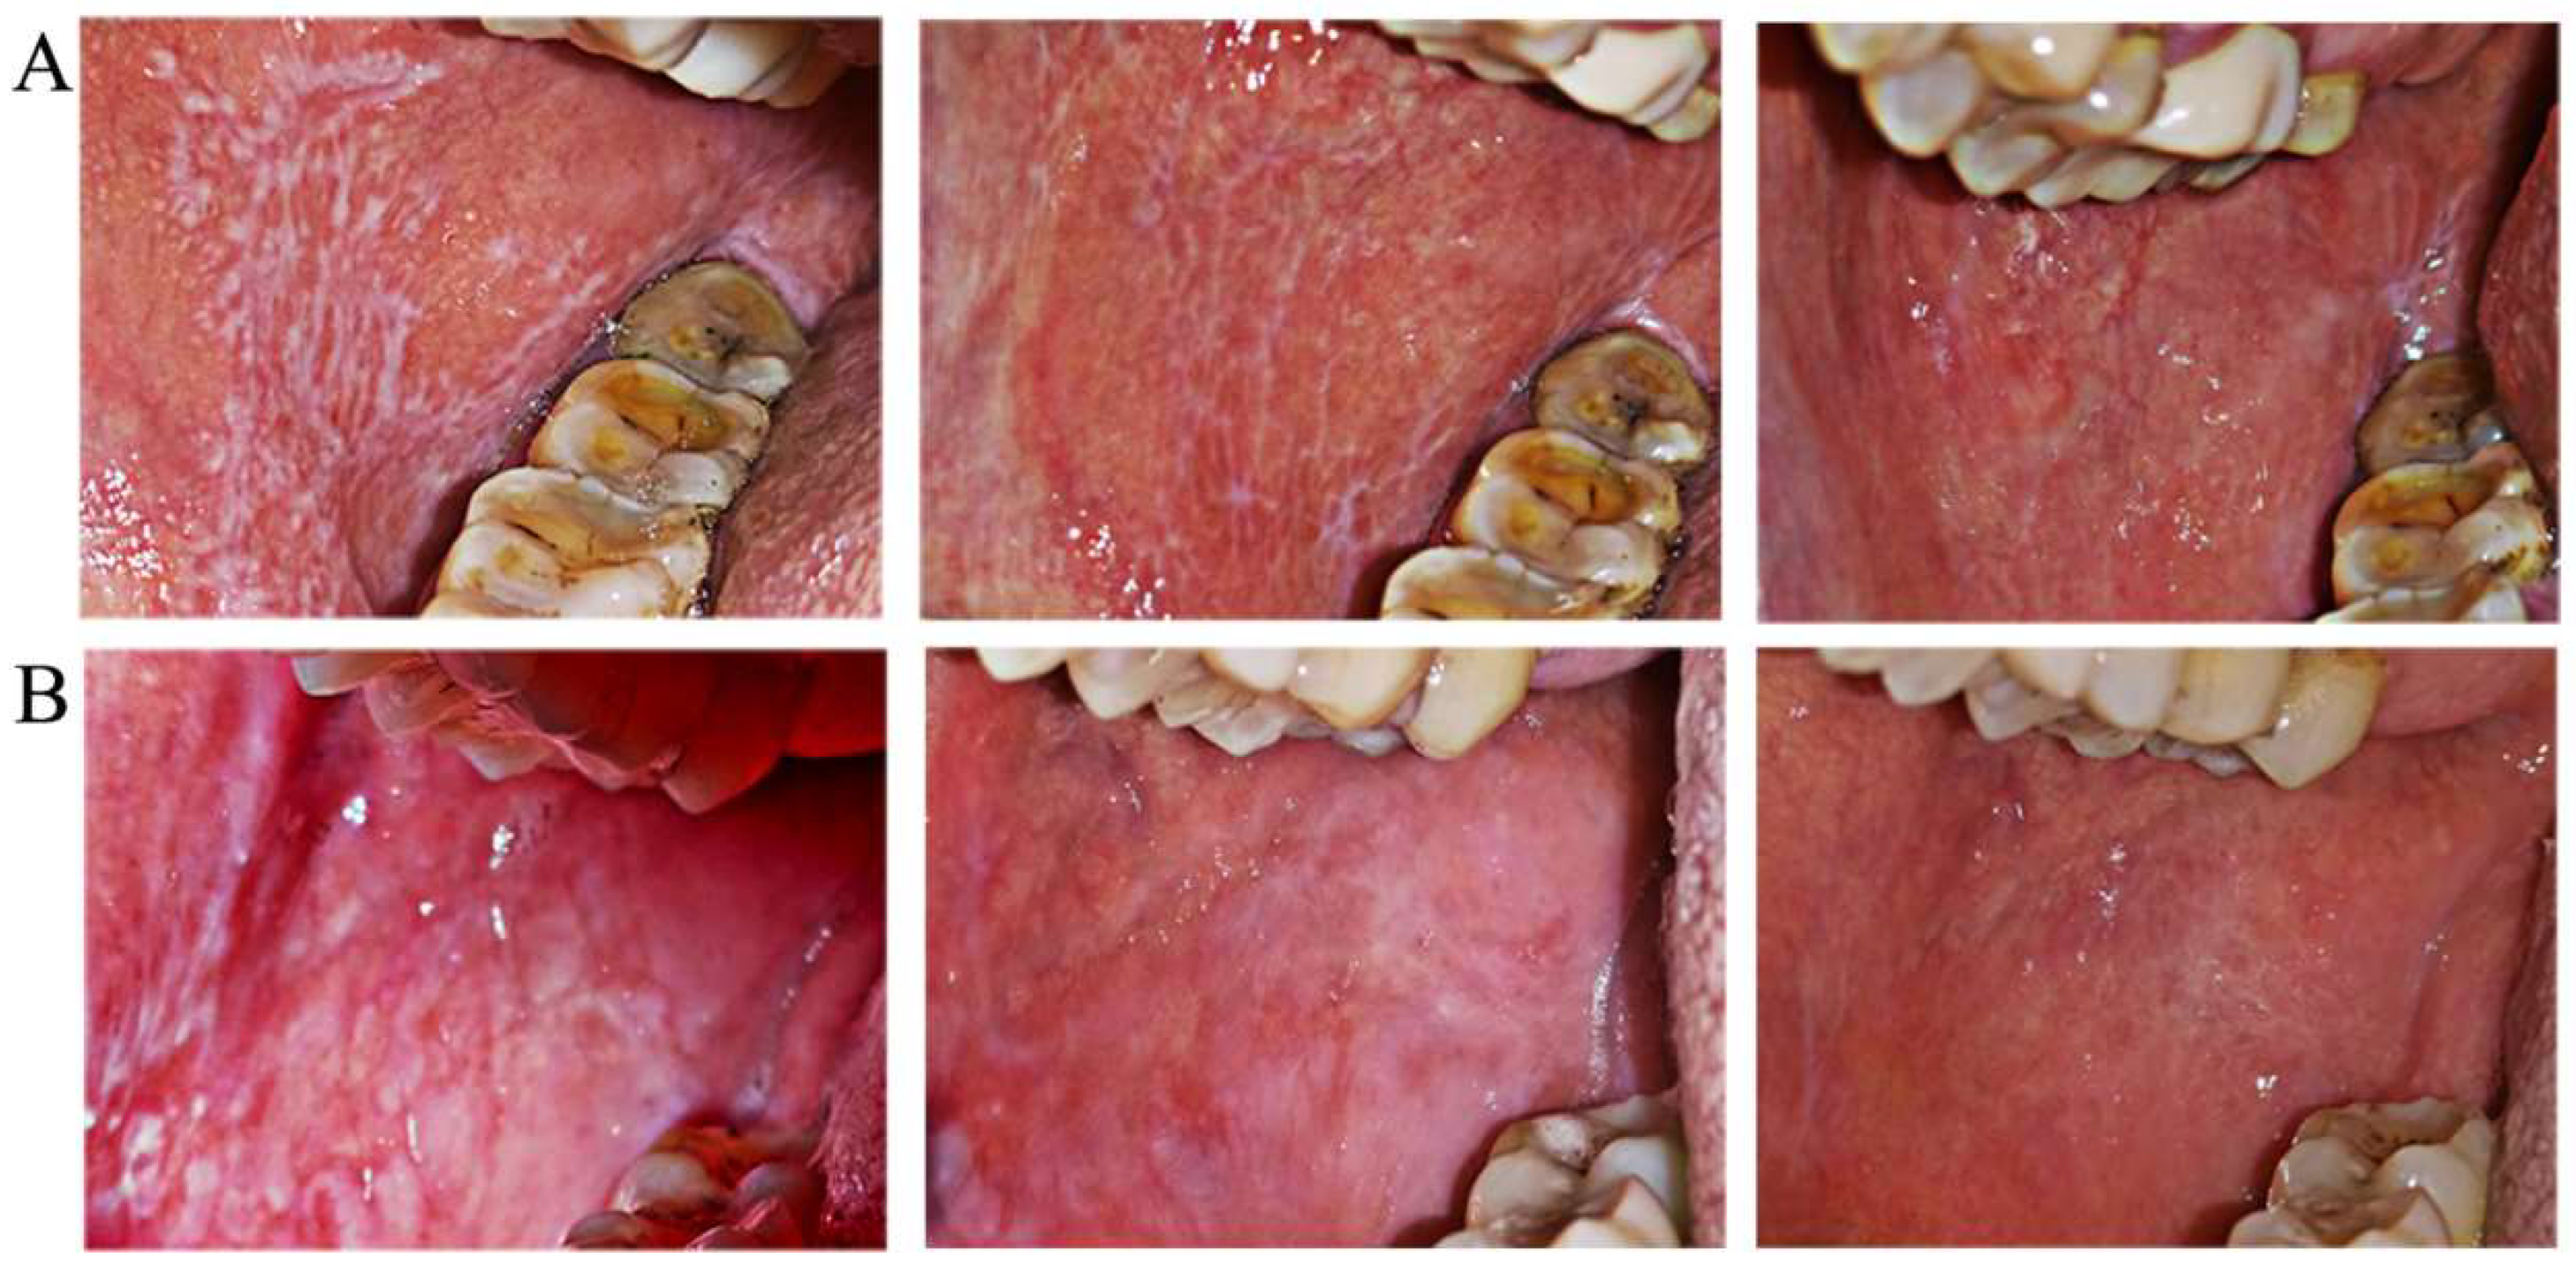

2.3. Clinical Recording